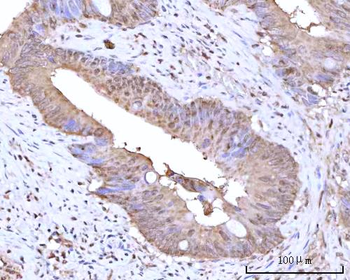

IHC staining of FFPE human lymph node with CD72 antibody (clone BU40). HIER: boil tissue sections in pH9 10mM Tris with 1mM EDTA for 20 min and allow to cool before testing.

IHC staining of FFPE human lymph node with CD72 antibody (clone BU40). HIER: boil tissue sections in pH9 10mM Tris with 1mM EDTA for 20 min and allow to cool before testing.